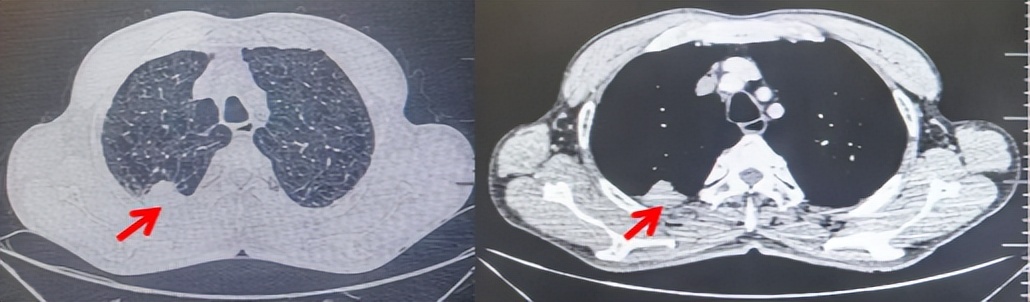

69岁男性,无糖尿病、高血压、心脏病等基础疾病,无吸烟、饮酒史,无肿瘤家族史。2023.06.07行胸部CT检查:右肺上叶胸膜下见肿物影,大小约33mm×22mm,边缘可见分叶,考虑恶性病变可能性大,双肺间质改变(如图1)。2023.06.14行“单孔胸腔镜下右肺上叶切除、肺门及纵隔淋巴结清扫、胸膜粘连松解术”;术后病理:(右肺上叶)腺癌(低分化,实体型占60%,不良腺体占40%),局灶伴神经内分泌标记表达(CD56、Syn),可见STAS及胸膜侵犯,未见确切神经侵犯及脉管内癌栓;(气管切缘)净;(淋巴结)未见转移癌0/26(2组0/2;4组0/6;7组0/2;对侧7组0/8;10组0/2;11组0/3;12组0/2;13组0/1)。术后分期pT2aN0M0 IB期,术后NGS基因检测:无驱动基因突变,PD-L1(22C3)TPS<1%。术后定期复查。

图1:患者手术前(2023.06)胸部CT肺窗及纵隔窗